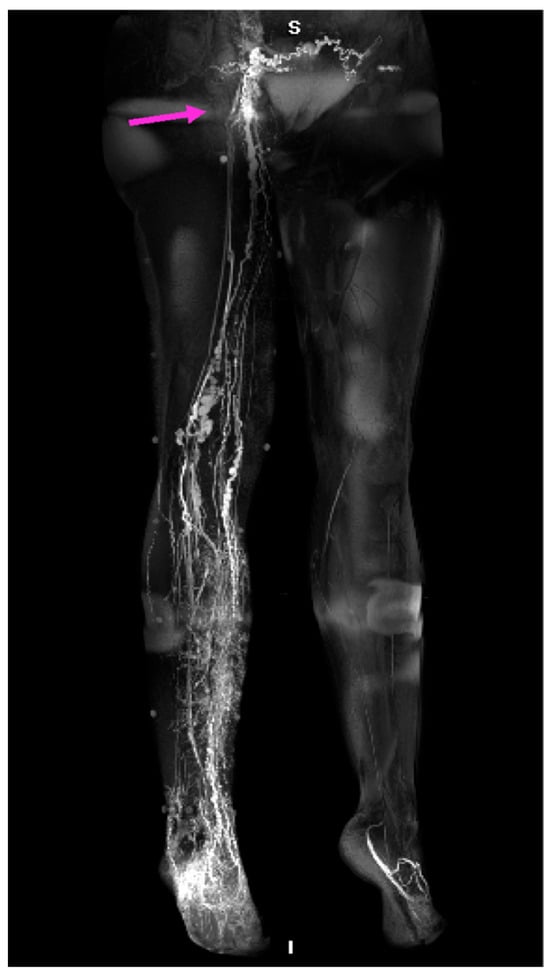

- Yamamoto, T.; Narushima, M.; Doi, K.; Oshima, A.; Ogata, F.; Mihara, M.; Koshima, I.; Mundinger, G.S. Characteristic Indocyanine Green Lymphography Findings in Lower Extremity Lymphedema: The Generation of a Novel Lymphedema Severity Staging System Using Dermal Backflow Patterns. Plast. Reconstr. Surg. 2011, 127, 1979–1986. [Google Scholar] [CrossRef]

- Yamamoto, T.; Matsuda, N.; Doi, K.; Oshima, A.; Yoshimatsu, H.; Todokoro, T.; Ogata, F.; Mihara, M.; Narushima, M.; Iida, T.; et al. The Earliest Finding of Indocyanine Green Lymphography in Asymptomatic Limbs of Lower Extremity Lymphedema Patients Secondary to Cancer Treatment: The Modified Dermal Backflow Stage and Concept of Subclinical Lymphedema. Plast. Reconstr. Surg. 2011, 128, 314e–321e. [Google Scholar] [CrossRef]

- Yamamoto, T.; Yamamoto, N.; Doi, K.; Oshima, A.; Yoshimatsu, H.; Todokoro, T.; Ogata, F.; Mihara, M.; Narushima, M.; Iida, T.; et al. Indocyanine Green-Enhanced Lymphography for Upper Extremity Lymphedema: A Novel Severity Staging System Using Dermal Backflow Patterns. Plast. Reconstr. Surg. 2011, 128, 941–947. [Google Scholar] [CrossRef]